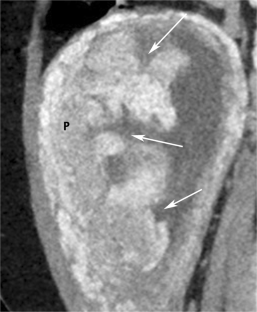

Fig. 3